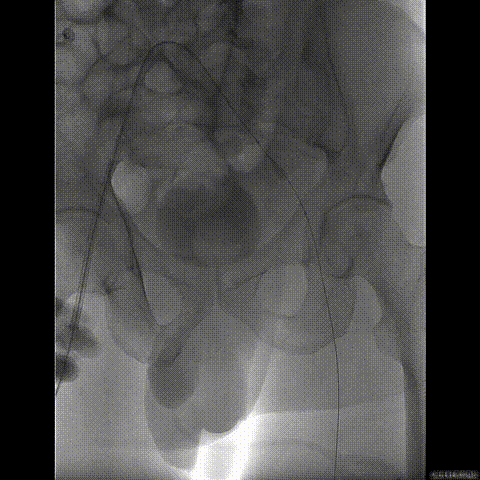

行急诊手术 腹主动脉及左侧股动脉造影

左侧股动脉见造影剂外渗

球囊压迫后植入覆膜支架

复查造影